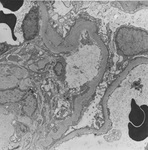

Diabetic kidney disease

Diabetic kidney disease: at 5 o'clock - early Kimmelstiel-Wilson nodule, a rounded increase in mesangial matrix that probably originated in relation to a microaneurysm

From the collection of Dr Raoul Fresco; used with permission